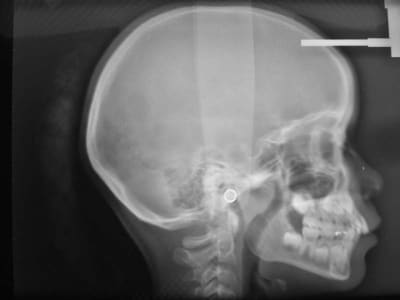

Avant TTT.

à suivre Bjc.

c'est le mm. patiente

la coloration des dents est assez remarquable

P.S.: j'avais à l'époque un Fuji mono-objectif

les photos de la contention ont été prises avec un Canon 1000 objectif Macro

les couleurs ne sont pas tout à fait les mm.

mais les dents ont gardé la mm. forme et les taches sont reconnaissables

@+ Bjc.